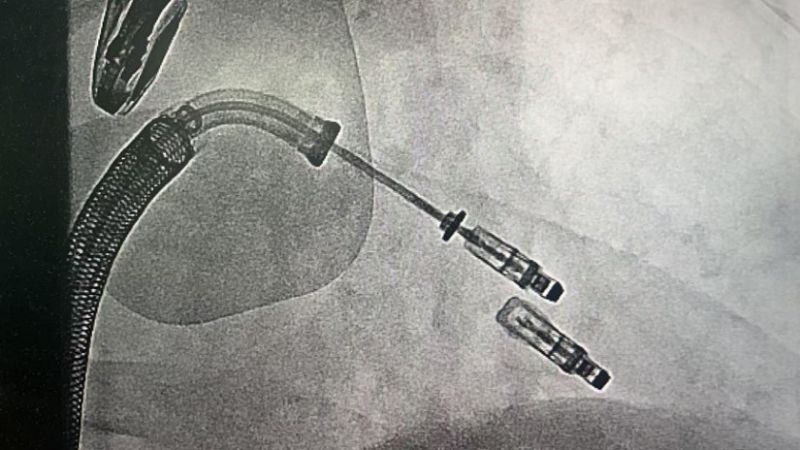

手術(shù)于11月4日下午進(jìn)行,通過(guò)股靜脈穿刺送入夾合器,在食道超聲實(shí)時(shí)引導(dǎo)下,精準(zhǔn)植入2枚瓣膜夾修復(fù)二尖瓣。整個(gè)過(guò)程歷時(shí)約2小時(shí),術(shù)中出血量?jī)H50ml。術(shù)后次日,患者即可下床活動(dòng),復(fù)查顯示EF提升至46%,二尖瓣返流面積縮小至3.0cm2,左心房縮小至66mm,胸悶、氣短癥狀明顯緩解。

1.微創(chuàng)路徑:經(jīng)股靜脈穿刺,無(wú)需開(kāi)胸或體外循環(huán);

2.精準(zhǔn)定位:在食道超聲和X線引導(dǎo)下,將夾合器送達(dá)二尖瓣位置,通過(guò)夾合病變瓣膜減少返流;